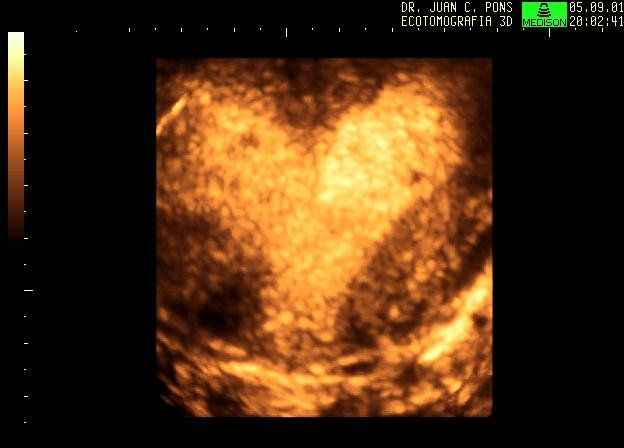

4D image of 29 weeks pregnancy, multiple anomalies: Clinch hand, omphalocoele, single atrium